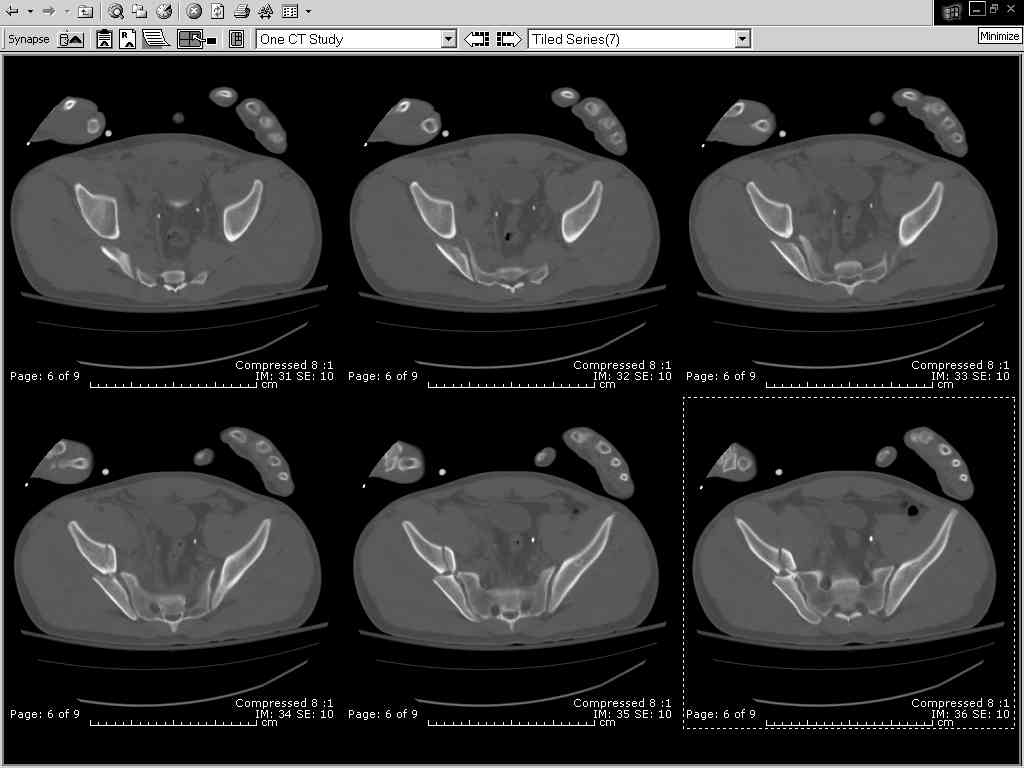

Thanks Adam - I agree it's not a pure APC (is there really such thing as a pure force vector strictly in the x,y or z plane?). I stand corrected. Maybe a hybrid APC (ext rot of L hemipelvis, symphysis disruption, ext rot of R anterior innominate) plus vertical shear as well with 3 or-so cm of cephalad migration of the R ilium. Maybe just "C-type".....

It almost looks to me like an extra-articular both column fx, in addition to the pelvic component. It has the typical triangular fragment and the OO view has a hint of the spur. You may be able to get it all with plates. I would consider fixing the crest first, then a long plate for both symph and iliac portion. SI may close with reduction of symphisis. Looks like the inferior portions are intact. I like your plan as well. You will probably solicit lots of opinion. Good luck. Look forward to post op view.

So, there I was with the aforementioned info on my mind, and my R iliac wing was a little malreduced. I think it's in residual extension and some external rotation, explaining the 5-6mm gap/step

on the posterior R iliac wing. (When I loooked at the inlet fluoro, the L obturator foramen was more visible than the R obt foramen, as was the R ischial spine) so it's not as stable as if it were

anatomic, despite all the metal. This came from hesitance to take down all the posterior paraspinals to really see the R posterior crest (where the malreduction is best seen on the iliac oblique view), and I could see the entire iliac fossa and most of the crest anyway.